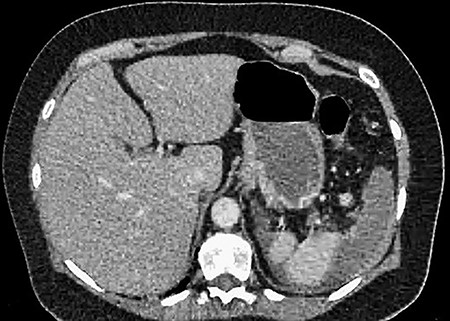

A 61-year-old female presented to a regional hospital with a 3-week history of intermittent diarrhoea, vomiting and generalized abdominal pain. She had a diffusely tender abdomen but was not peritonitic, and was shocked with a heart rate of 110 beats per minute, blood pressure of 89/45 mmHg and was peripherally cool. Her blood tests revealed a lactate of 7.2 mmol/L, which worsened to 7.8 mmol/L during resuscitation with intravenous fluids, and white cell count was 30.9 × 109/L, with an international normalized ratio (INR) of 1.4. She had an acute kidney injury with a creatinine of 119μmol/L and estimated glomerular filtration rate (eGFR) of 43 mL/min/1.73m2. Computed tomography (CT) revealed extensive thickened loops of non-enhancing small bowel with pneumatosis, moderate free fluid and a large splenic infarction. There was extensive thrombosis of the splenic vein and superior mesenteric vein extending into the portal vein to the level of the porta hepatis. Her background history included factor V Leiden and protein S deficiency, for which she had been non-compliant with warfarin during this illness. She had no surgical history (Figs. 1–5).

CT showing an area of splenic infarction due to venous ischaemia.